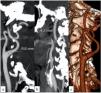

Material and methodsIn total 300 patients who had supra-aortic computed tomography angiography (CTA) were enrolled in this study from 2015 to 2021. The study groups consisted of 100 ischemic stroke patients, 100 patients with intracranial aneurysms, and 100 control subjects. The intracranial aneurysm patient group was divided into two subgroups according to the presence of subarachnoid hemorrhage (SAH). The largest diameters of the ICA C1 (cervical) and C2 (petrous) segments in all individuals were measured bilaterally on CTA images. The ICA diameter ratios of the cases were measured using the formula (C1-C2)/C1. The relationship between the age and ICA vessel analysis was evaluated as well.

ResultsThe mean ICA bulb width values in the ischemic stroke patient group and the intracranial aneurysm patient group were significantly higher than the control group (P<.001). The ICA C1 and C2 segment diameter values and ICA diameter ratio were smaller in the intracranial aneurysm patients with SAH than those who had not (P= 0.7). There was a statistically significant but weak relationship between the age and ICA diameter ratios in all study groups (R-squared value of 0.26, P= 0.03).